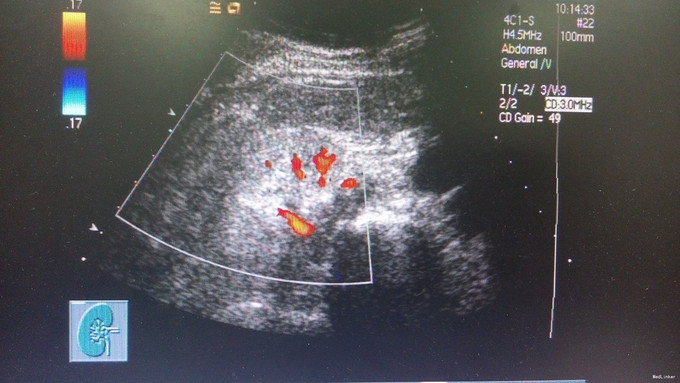

查体:血压135/84mmHg,双下肢可凹性浮肿,眼结膜苍白。 辅查:肌酐924.00umol/L,铁5.7umol/L,总铁结合力30.5umol/L,血红蛋白73g/L,尿素32.13mmol/L,尿酸499umol/L。 肾脏B超显示慢性肾功能不全声像,双肾缩小。对患者进行肾小球滤过率估计:eGFR为4mL/min/1.73mE2。